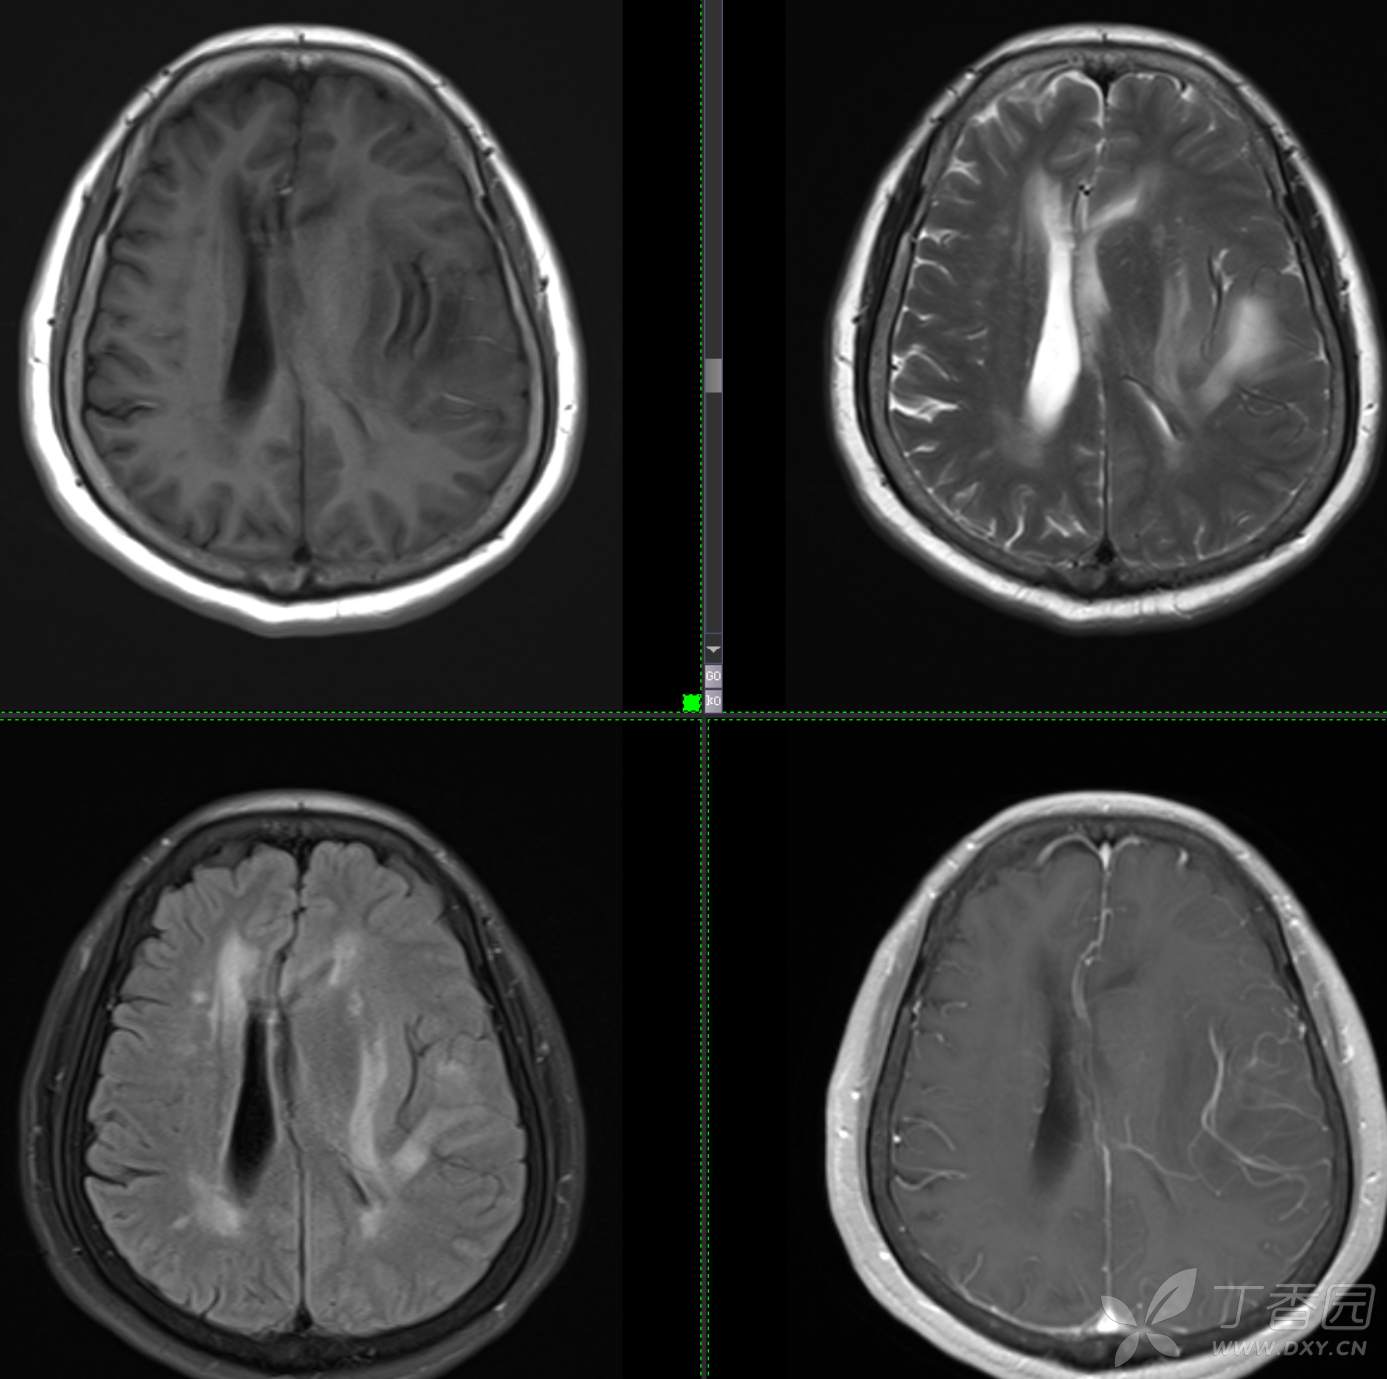

现病史: 【患者1月余前无明显诱因出现记忆力减退,易忘记事情,表现为忘记说过的话、易忘 事、理解力及计算力均尚可、阅读无受限、无性格脾气改变,无头痛头晕、无恶心呕吐、无视物模糊,无言语不利,无幻觉妄想,当时未重视未就诊。1月内记忆力减退进行性加重,对刚做过的事情即遗忘,计算力下降,日常生活尚能自理。遂至我院门诊就诊,查“颅脑CT平扫:左侧基底节-颞叶区低密度占位,建议进一步增强 MRI检查。

患者既往子宫内膜癌手术史;高血压病史3年